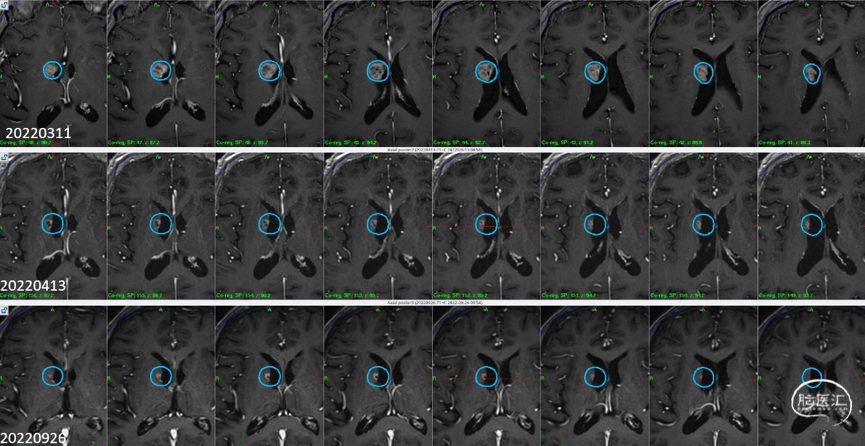

2)右侧侧脑室壁病灶体积缩小显著:

6个月随访

影像随访:

1)左额病灶:囊性病变逐渐缩小

6个月随访时,薄扫增强磁共振(1mm/层)提示肿瘤明显缩小,无放射相关不良反应,没有新发病灶;患者目前仍在规律的随访当中,期待我们的长期随访结果。